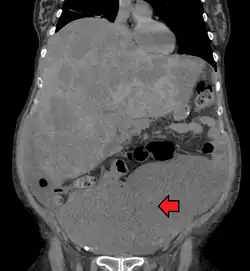

Colon cancer with extensive metastases to the liver

Colorectal cancer diagnosis is performed by sampling areas of the colon suspicious for possible tumor development, typically during colonoscopy or sigmoidoscopy, depending on the location of the lesion.[20]

Medical imaging

A colorectal cancer is sometimes initially discovered on CT scan.[95]

The presence of metastases is determined by a CT scan of the chest, abdomen, and pelvis.[20] Other potential imaging tests such as PET and MRI may be used in certain cases.[20] MRI is particularly useful to determine the local stage of the tumor and to plan the optimal surgical approach.[95]